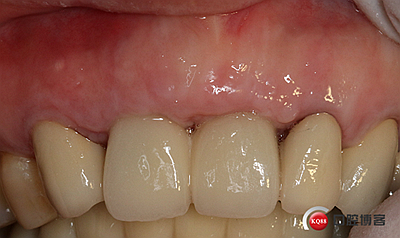

戴牙。

戴牙后半年復(fù)查。